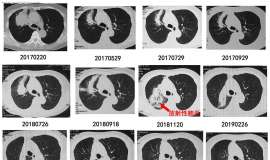

EGFR18

父亲今年七月份确诊肺腺癌,基因检测 EGFR18突变。可惜没有靶向药。目前在盲吃,吃了两个月吉非替尼,CEA没有任何波动,压迫喉返神经。伏美替尼半个月,依旧没有变化。目前伏美替尼跟阿法替尼交替吃。 我的父亲一辈 ...